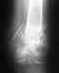

Мне 31 год.28.01 09. получил закрытый перелом большеберцовой кости со смещением.3.02.09 проведен остеосинтез большеберцовой кости блокирующим стержнем.При выписке получил письменную рекомендацию-динамизировать через 4-5недель.Участковый травматолог, уходя в отпуск, на вопрос о том, что такое динамизация бросил: винтик какой-то должны выкрутить. Все!!! какой, когда, зачем-непонятно.На снимках от 27.04. отчетливо видно место перелома.Рекомендовали кальций и мумие в теч. 10 дней( всего?!). Я пил 2 месяца.РЕзультат нулевой. Сегодняшние снимки прокомментированы так: отчетливо просматривается место перелома, явно выраженный остеопороз.Сейчас хожу с одним костылем около двух недель,при длительной ходьбе появляются боли в стопе, очень редко -в месте перелома.Больше ничего не беспокоит. Могу пройти немного по квартире без костылей.Вопрос: нужна ли мне динамизация и что делать с остеопарозом? Насколько я понял из прочитанных в интернете статей и обсуждений, остеопороз невозможно выявить по снимкам -нужен анализ плотности костной ткани.Зачем же так безапелляционно заявлять о его наличии?

я не вижу снимка, но скажу одно-динамизация нужна, обычно через 7-8 недель,а для того чтобы винт в стержне не сломался после нагрузки на ногу. винт убирается, и разрешается полная нагрузка на конечность. а по поводу остеопороза, он есть потому, что конечность не испытывает должной нагрузки. хотя по правилам без снимка не обсуждают проблему.

Уже прошло 5 мес. после операции. Должно было срастись, если все идет по плану.

Никакого мумия и кальция в лечении перелома костей голени применять не нужно. С местным остеопорозом делать ничего не нужно. Нужно ли сейчас что-то делать с фиксатором (динамизировать ли, в частности), можно сказать после знакомства со рентгенограммой, отражающей сегодняшнюю ситуацию, а не апрельскую.